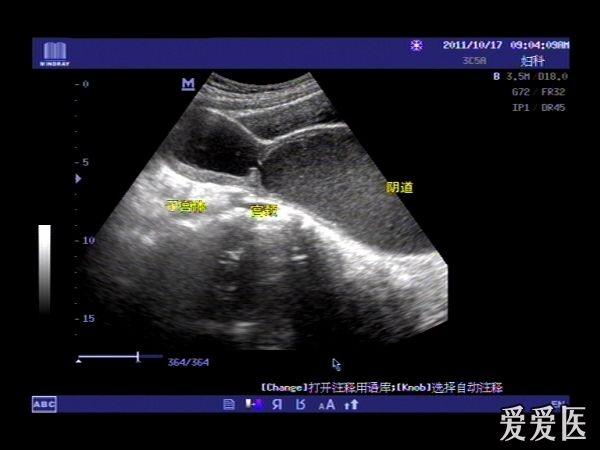

患者,女,14岁,因周期性下腹部胀痛不适3月余来我院就诊。查体:下腹部可扪及一包块。超声检查膀胱适度充盈,子宫前倾位,宫底部上移至脐平面,宫体宫腔,宫颈及**明显扩张呈椭圆形,内回声不纯净,呈细密的点状回声,宫内膜显示清晰。超声诊断处女膜闭锁